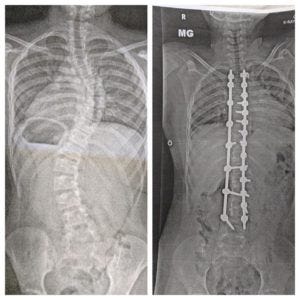

We left the hospital about 48 hours after we had checked in (at least two days earlier than we were expecting), but not before we were finally presented with an x-ray of what my son's spine now looks like. We had been told early on that his curves could be corrected to 15-20 degrees. Instead, we were pleasantly surprised to find that the curves are now virtually non-existent. It was an amazing sight.